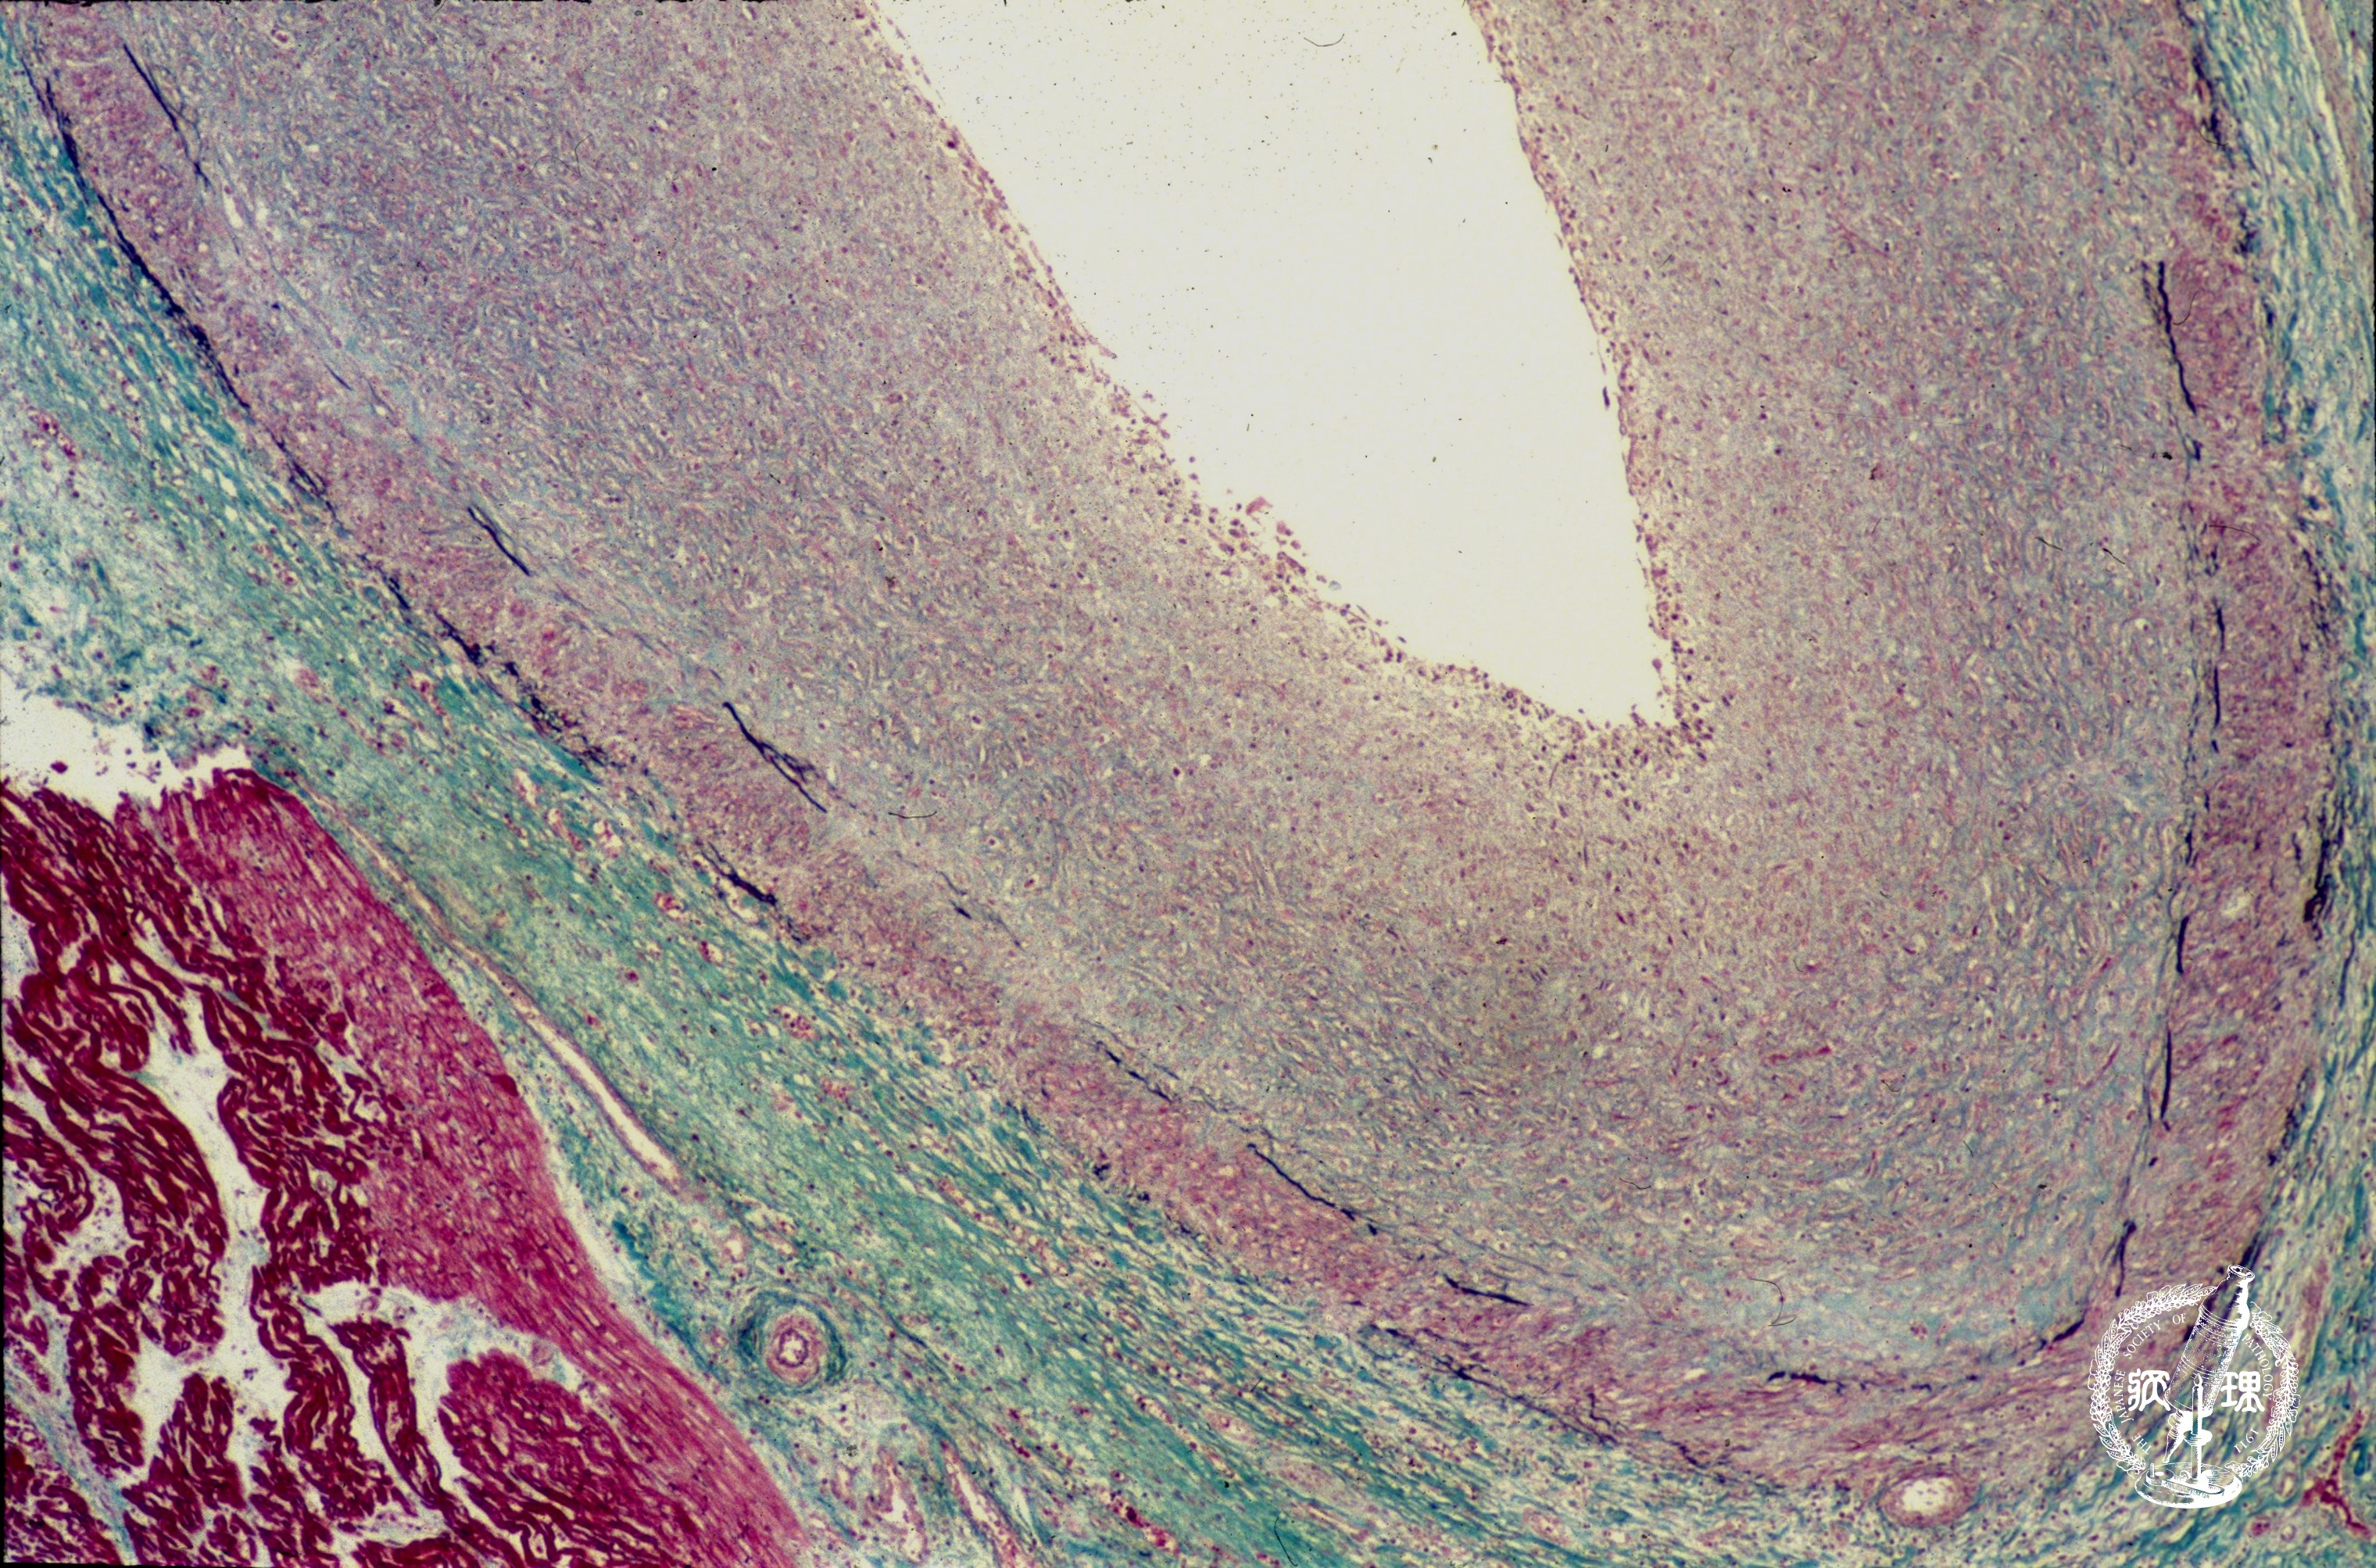

(15)川崎病

マクロ像:左前下行枝の起始部に拡張を認める。罹患児の十数パーセントが冠動脈瘤を合併する。